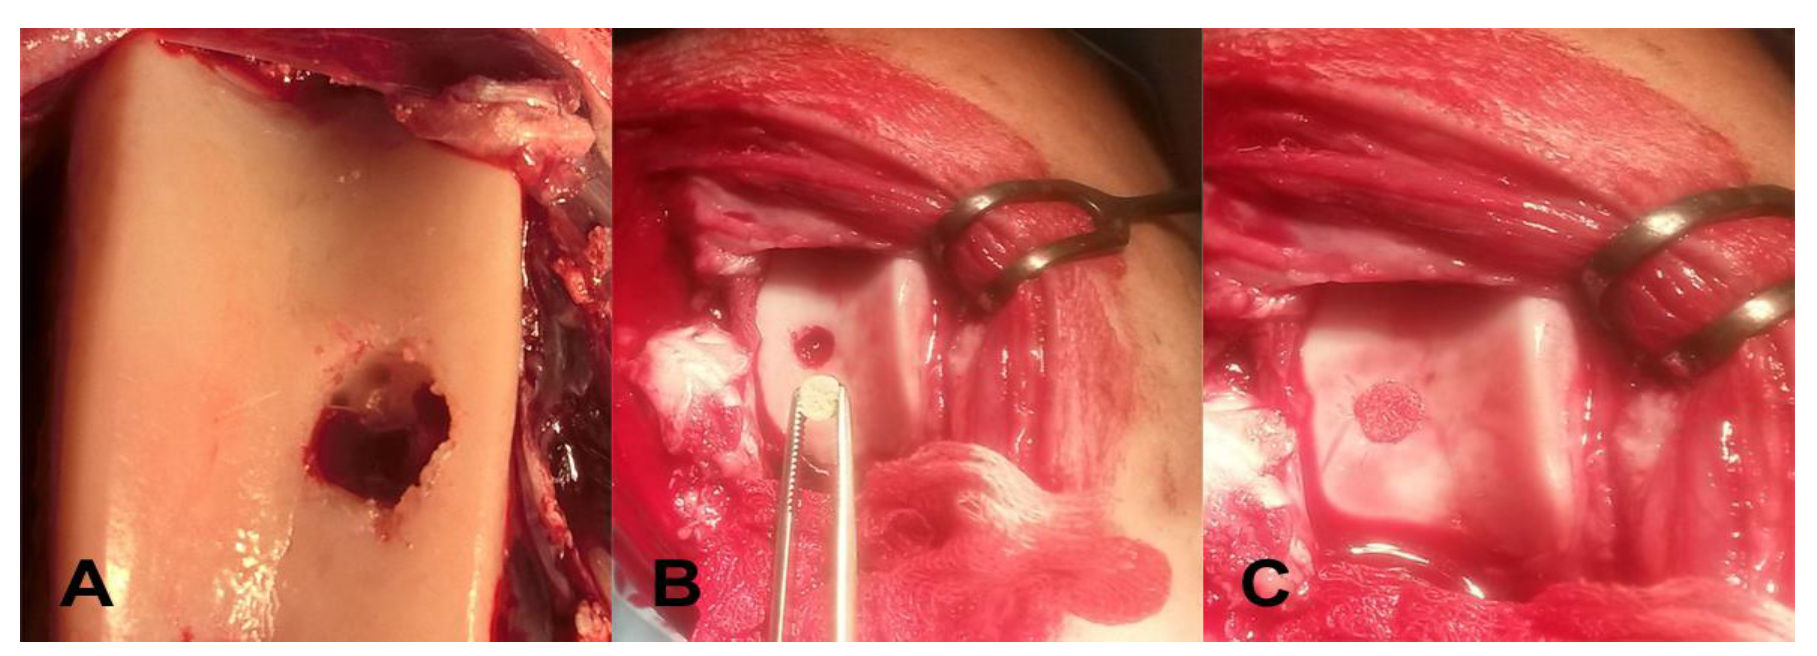

3.1. Macroscopic Evaluation of Repaired Cartilage Defects

3.2. X-ray Evaluation

2.3. Surgical Manipulation with Biopolymer Composites